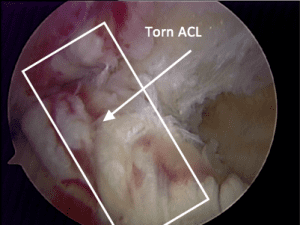

Photos below show a torn ACL (top) and the reconstructed ligament from a cadaver allograft (bottom).